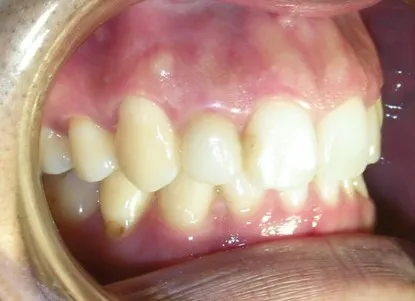

<<三年又三個月後的今天 陳先生回診>>

這顆Cap-Lock 依然這麼美觀而自然

牙齦的部份也沒有發炎或者變色

乍看之下,還真忘了它其實是顆我幫他做的Cap-Lock假牙,倒是遠心用樹脂填補的部份,三年多下來已經變色了!